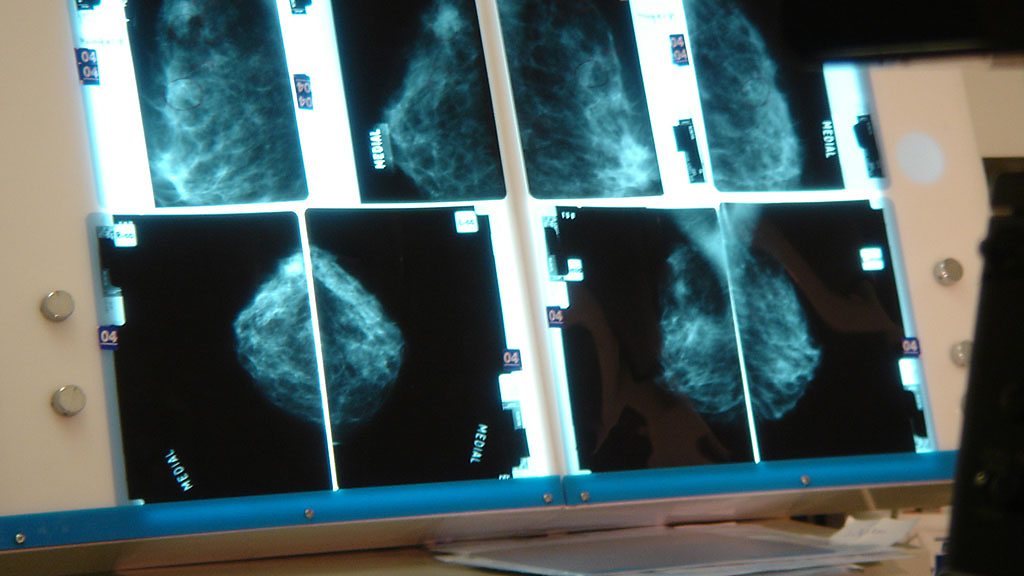

Prof Beral believes breast cancer could be cut significantly with a "hormonal vaccine".